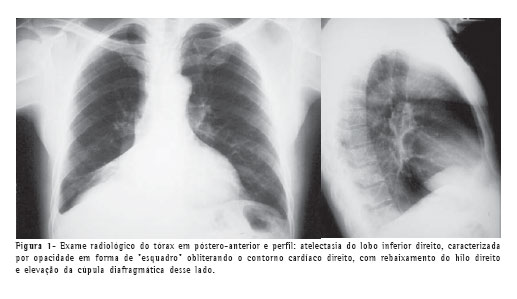

A tomografia computadorizada de tórax confirmou a atelectasia e mostrou pequena lesão calcificada em luz de brônquio no lobo inferior direito (Figura 2), além de bronquiectasias com provável impactação mucóide no lobo pulmonar colapsado.

As radiografias do tórax nas incidências póstero-anterior e perfil evidenciaram sinais de redução volumétrica do lobo inferior direito, com borramento do contorno cardíaco desse lado (Figura 1).